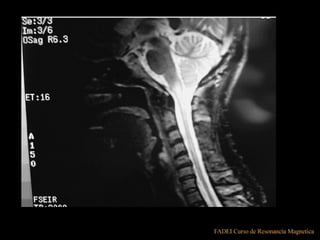

*FLAIR

*FLAIR (fluid attenued inversion recovery)

• TI= LARGO PARA SATURAR EL AGUA,

• Para evaluar focos isquémicos

ENF DESMIELINIZANTES

SE VE LA ISQUEMIA

EN SUST. BLANCA

FLAIR

EL AGUA

DIO SEÑAL?

¿COMO SE VE

LA SUST. GRIS?

COMPARADO

CON UN T1

LA SUST. BLANCA?